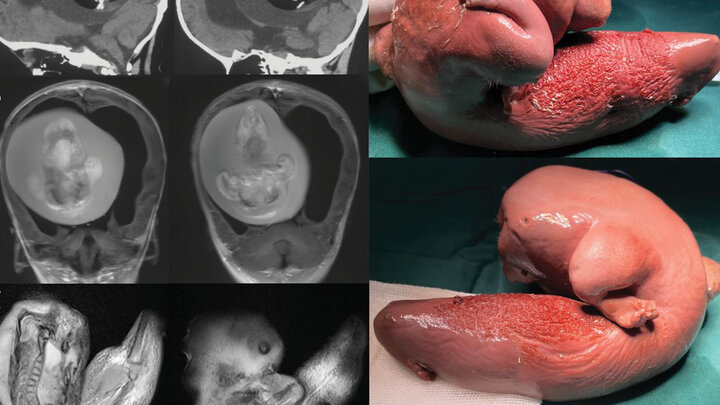

به گزارش شفا آنلاین:پزشکان دانشگاه فودان در شانگهای متوجه چند مشکل در یک دختربچه یک ساله مانند سر بیش از حد بزرگ و اختلال در مهارت های موتور حرکتی شدند. به نوشته نشریه IFLScience سی تی اسکن های سر این دختر بچه نشان داد مغز او تحت فشار است. علاوه بر آن تجمع مایعات سبب رشد بیش از اندازه در بطن های مغز شده بود.

محققان طی فرایند جراحی متوجه شدند رشد بطنی در حقیقت قل متولد نشده این کودک بوده است. هرچند بخش اعظم جنین تکامل نیافته بود اما به نظر می رسید اعضای بخش بالایی بدن و اندام های فرعی مانند انگشتان شکل گرفته اند.

چنین مواردی در متون پزشکی بسیار نادر هستند. موارد جنین داخل جنین در مراحل اولیه بارداری دوقلوها و زمانی اتفاق می افتد که بلاستوسیست( خوشه ای از سلول های در حال جدا شدن به وسیله تخمک بارور) به درستی انجام نمی شود.

در نتیجه این امر یکی از جنین ها دیگری را دربر می گیرد. هرچند باید اشاره کرد جنین دربرگرفته شده نمی میرد بلکه به دلیل خون رسانی منظم از قل دیگر، زنده می ماند اما رشد نمی کند.